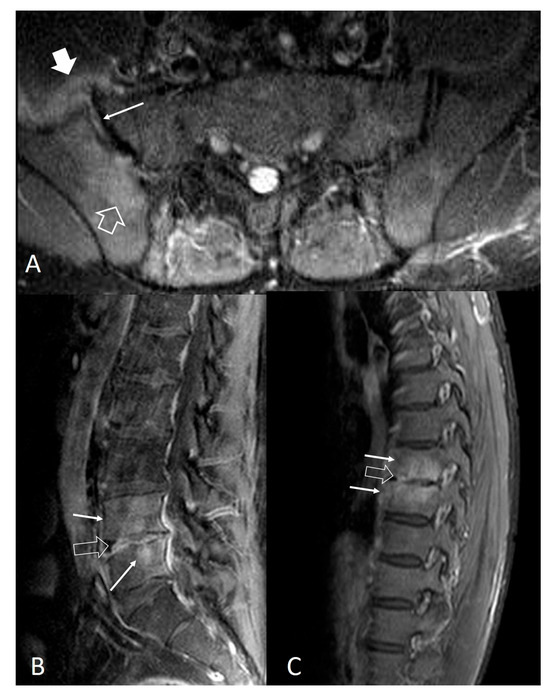

- Bozgeyik, Z.; Ozdemir, H.; Demirdag, K.; Ozden, M.; Sonmezgoz, F.; Ozgocmen, S. Clinical and MRI findings of brucellar spondylodiscitis. Eur. J. Radiol. 2008, 67, 153–158. [Google Scholar] [CrossRef]

- Bozgeyik, Z.; Aglamis, S.; Bozdag, P.G.; Denk, A. Magnetic resonance imaging findings of musculoskeletal brucellosis. Clin. Imaging 2014, 38, 719–723. [Google Scholar] [CrossRef]

- Ozaksoy, D.; Yucesoy, K.; Yucesoy, M.; Kovanlikaya, I.; Yuce, A.; Naderi, S. Brucellar spondylitis: MRI findings. Eur. Spine J. 2001, 10, 529–533. [Google Scholar] [CrossRef] [PubMed]

- Harman, M.; Unal, O.; Onbasi, K.T.; Kiymaz, N.; Arslan, H. Brucellar spondylodiscitis: MRI diagnosis. Clin. Imaging 2001, 25, 421–427. [Google Scholar] [CrossRef] [PubMed]

- Chelli Bouaziz, M.; Ladeb, M.F.; Chakroun, M.; Chaabane, S. Spinal brucellosis: A review. Skelet. Radiol. 2008, 37, 785–790. [Google Scholar] [CrossRef]

- Raptopoulou, A.; Karantanas, A.H.; Poumboulidis, K.; Grollios, G.; Raptopoulou-Gigi, M.; Garyfallos, A. Brucellar spondylodiscitis: Noncontiguous multifocal involvement of the cervical, thoracic, and lumbar spine. Clin. Imaging 2006, 30, 214–217. [Google Scholar] [CrossRef] [PubMed]

- Sharif, H.S.; Clark, D.C.; Aabed, M.Y.; Haddad, M.C.; al Deeb, S.M.; Yaqub, B.; al Moutaery, K.R. Granulomatous spinal infections: MR imaging. Radiology 1990, 177, 101–107. [Google Scholar] [CrossRef]

- al-Shahed, M.S.; Sharif, H.S.; Haddad, M.C.; Aabed, M.Y.; Sammak, B.M.; Mutairi, M.A. Imaging features of musculoskeletal brucellosis. Radiographics 1994, 14, 333–348. [Google Scholar] [CrossRef]

- Guo, H.; Lan, S.; He, Y.; Tiheiran, M.; Liu, W. Differentiating brucella spondylitis from tuberculous spondylitis by the conventional MRI and MR T2 mapping: A prospective study. Eur. J. Med. Res. 2021, 26, 125. [Google Scholar] [CrossRef]

- Li, W.; Zhao, Y.H.; Liu, J.; Duan, Y.W.; Gao, M.; Lu, Y.T.; Yao, L.; Li, S.L. Imaging diagnosis of brucella spondylitis and tuberculous spondylitis. Zhonghua Yi Xue Za Zhi 2018, 98, 2341–2345. [Google Scholar] [CrossRef]

- Resorlu, H.; Sacar, S.; Inceer, B.S.; Akbal, A.; Gokmen, F.; Zateri, C.; Savas, Y. Cervical Spondylitis and Epidural Abscess Caused by Brucellosis: A Case Report and Literature Review. Folia Medica 2016, 58, 289–292. [Google Scholar] [CrossRef]